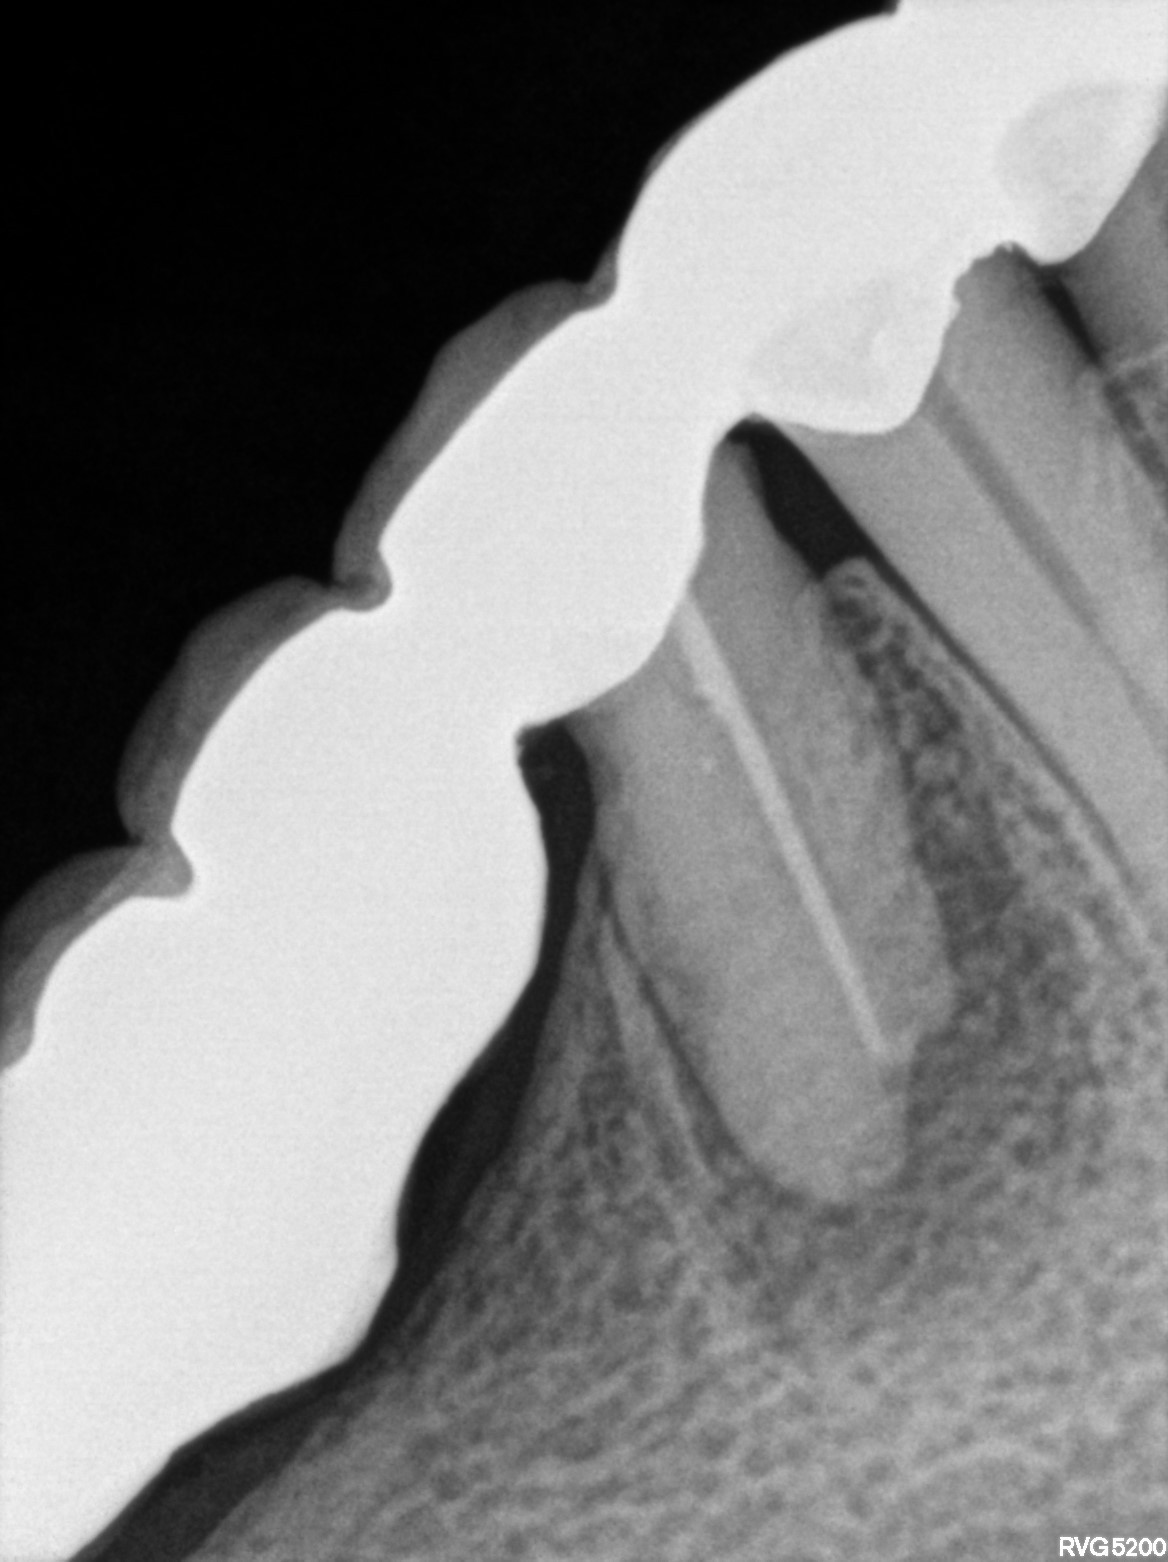

Dental Radiographs FHIR: DocumentReference · LOINC 24641-7

xray_1763362538_4.jpg

24641-7